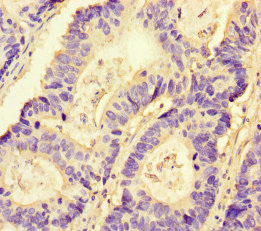

Immunohistochemistry of paraffin-embedded human colon cancer using CSB-PA016092LA01HU at dilution of 1:100